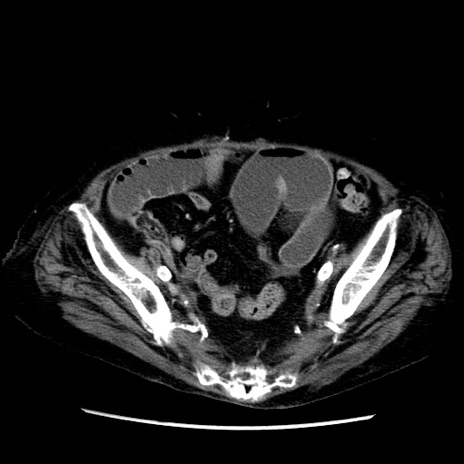

症例14(横断像)

【症例】 90歳代女性

【主訴】 腹痛・嘔吐

【現病歴】今朝から左側腹部痛を認めた。 経過観察していたが、嘔吐を認めたため来院。

【既往歴】 子宮癌術後

【身体所見】 意識清明、BP 127/54mmHg、P 98bpm Sp02 95%(RA)、BT 35.8°C、腹部平坦・軟腸ぜん動音聴取良好、右下腹部圧痛(+) 反跳痛なし

【データ】WBC 9800、CRP 0.46